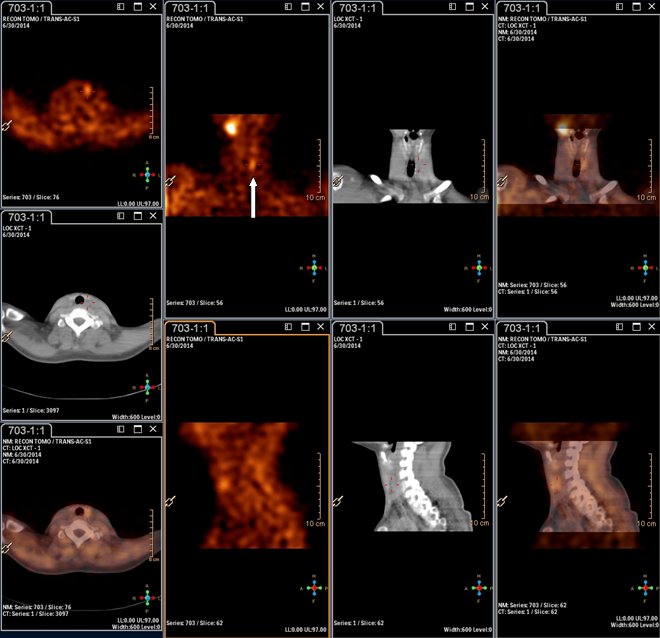

/ Obr.3.: Scintigrafie pomocí 99mTc-MIBI metodou SPECT/ldCT se zřetelnou patologickou ložiskovou depozicí

radiofarmaka v těsné blízkosti dolního pólu levého laloku štítné žlázy.